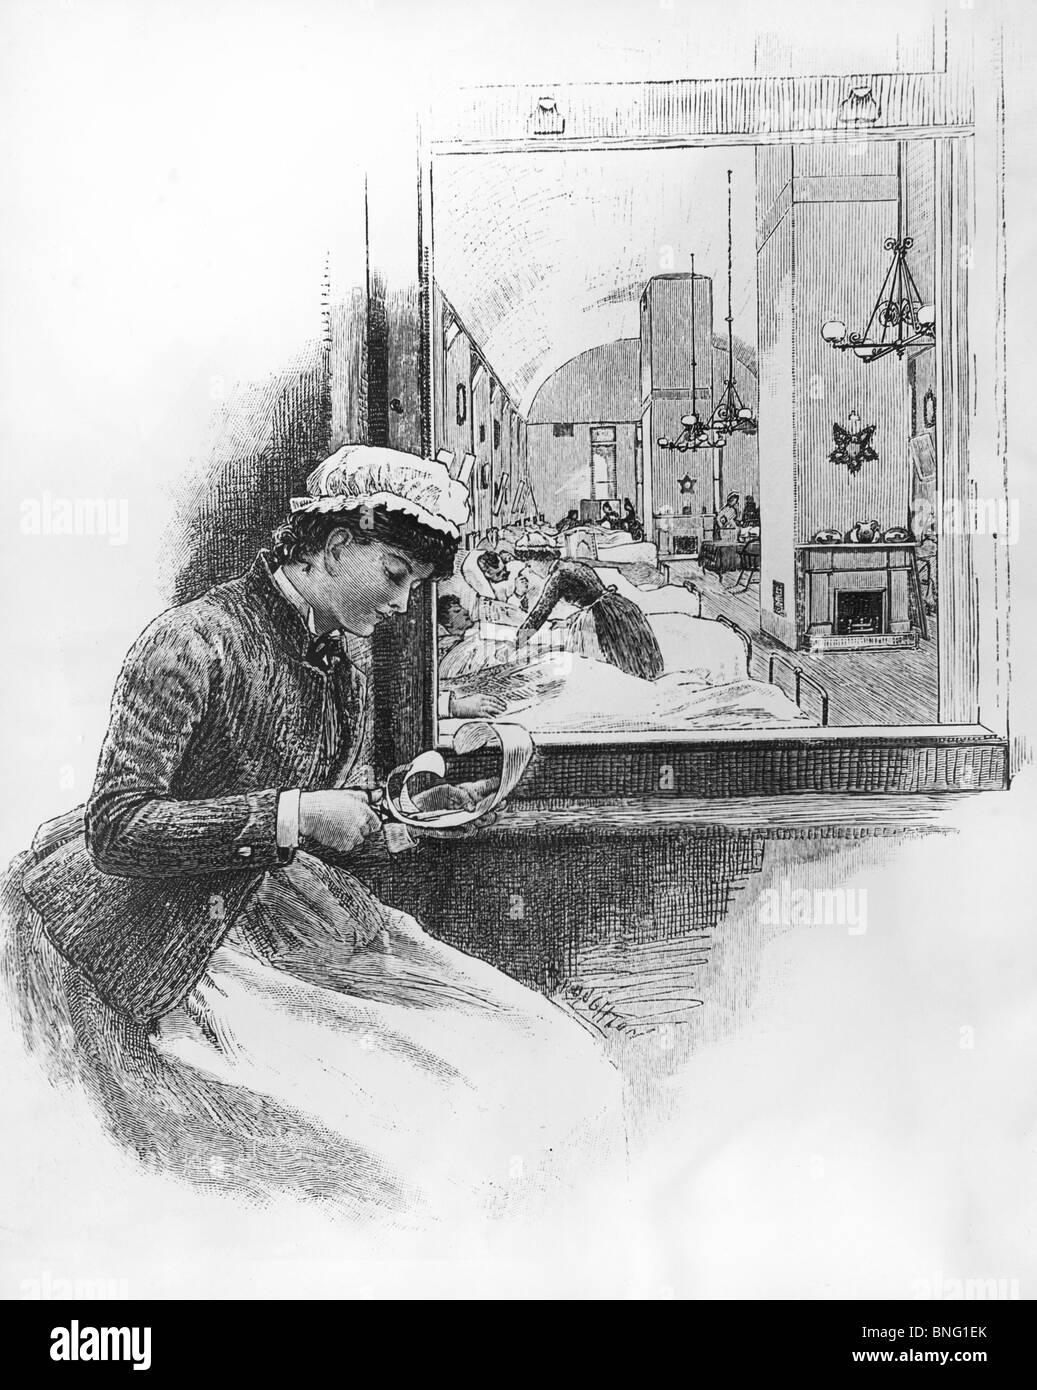

Kinderklinik, Bellevue Hospital von unbekannten Künstler Stockfotohttps://www.alamy.de/image-license-details/?v=1https://www.alamy.de/stockfoto-kinderklinik-bellevue-hospital-von-unbekannten-kunstler-30470575.html

Kinderklinik, Bellevue Hospital von unbekannten Künstler Stockfotohttps://www.alamy.de/image-license-details/?v=1https://www.alamy.de/stockfoto-kinderklinik-bellevue-hospital-von-unbekannten-kunstler-30470575.htmlRMBNG1ER–Kinderklinik, Bellevue Hospital von unbekannten Künstler

Geburt der amerikanischen Ausbildung Krankenschwester: der chirurgischen Abteilung im Bellevue Hospital in New York von unbekannten Künstlers Stockfotohttps://www.alamy.de/image-license-details/?v=1https://www.alamy.de/stockfoto-geburt-der-amerikanischen-ausbildung-krankenschwester-der-chirurgischen-abteilung-im-bellevue-hospital-in-new-york-von-unbekannten-kunstlers-30470571.html

Geburt der amerikanischen Ausbildung Krankenschwester: der chirurgischen Abteilung im Bellevue Hospital in New York von unbekannten Künstlers Stockfotohttps://www.alamy.de/image-license-details/?v=1https://www.alamy.de/stockfoto-geburt-der-amerikanischen-ausbildung-krankenschwester-der-chirurgischen-abteilung-im-bellevue-hospital-in-new-york-von-unbekannten-kunstlers-30470571.htmlRMBNG1EK–Geburt der amerikanischen Ausbildung Krankenschwester: der chirurgischen Abteilung im Bellevue Hospital in New York von unbekannten Künstlers